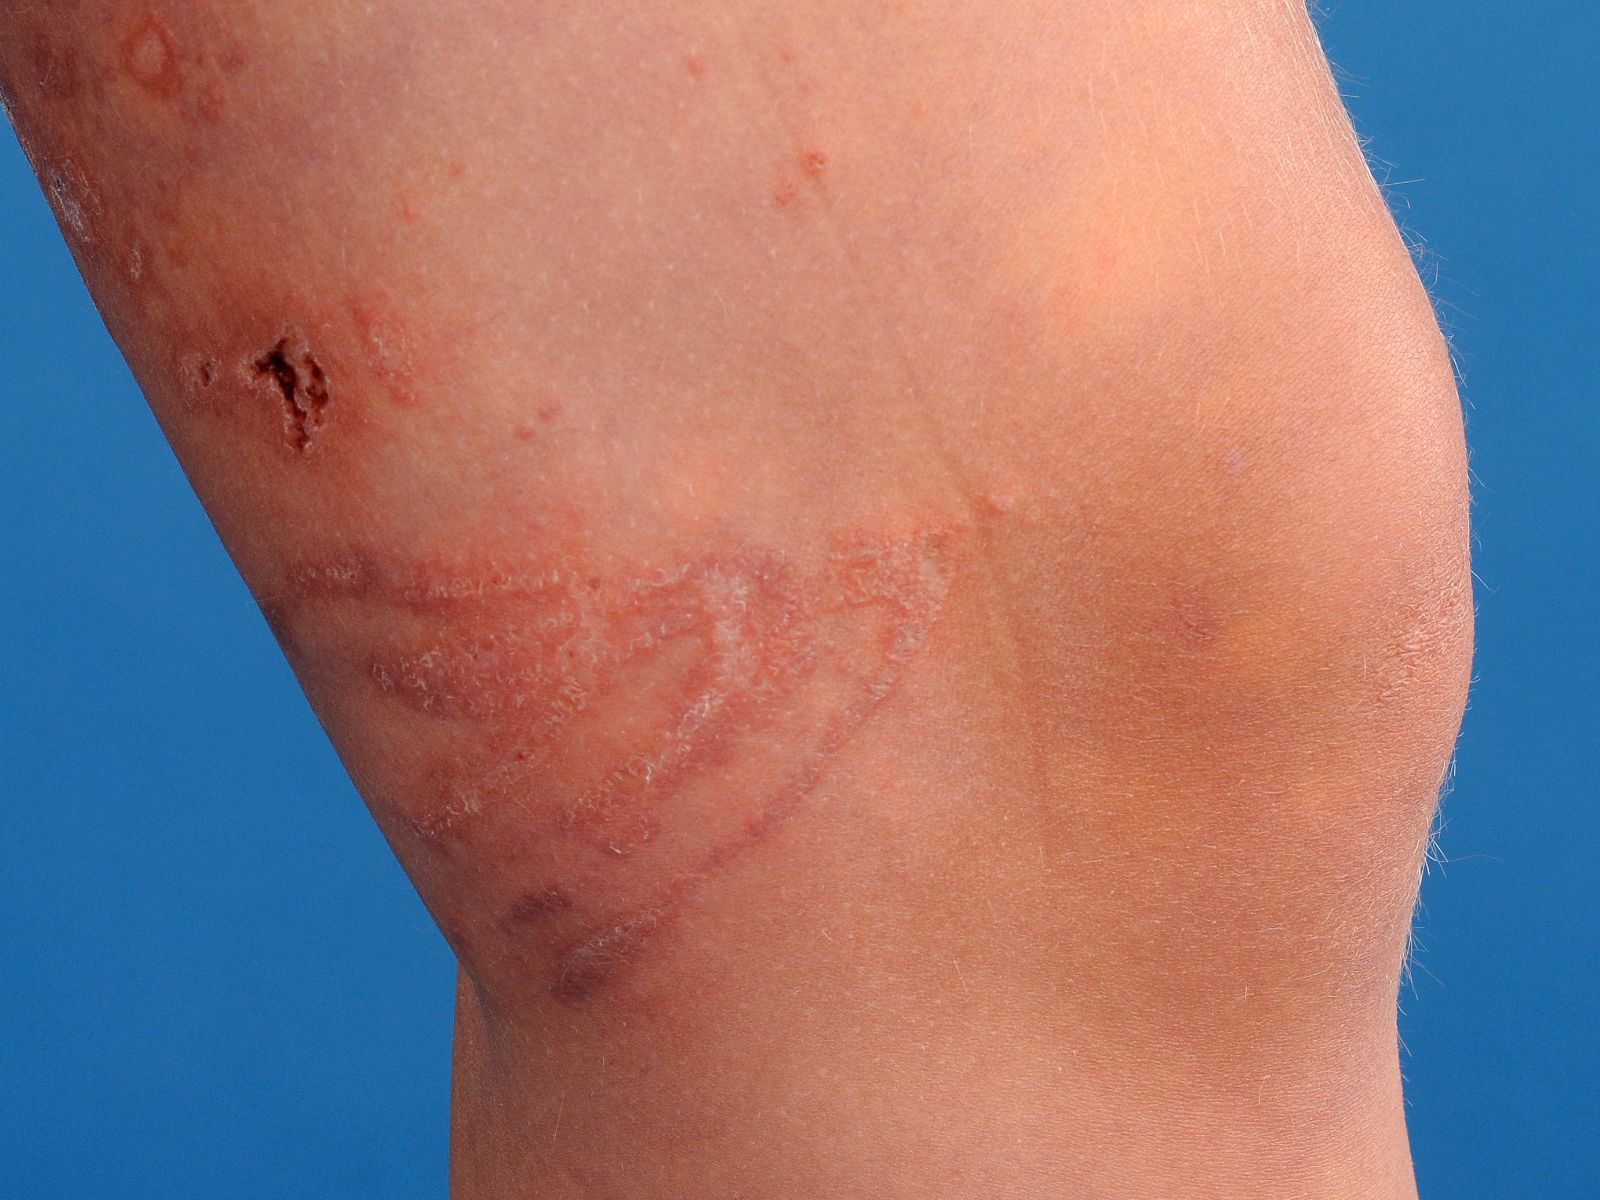

klassieke beeld bestaat uit pijnlijke, lineaire urticariële of vesiculopapuleuze

laesies. Ulceratieve, hemorragische of necrotische laesies zijn echter ook mogelijk.

De laesies ontstaan acuut en zijn binnen een aantal minuten tot uren weer verdwenen.

Secundair aan de initiële huidlaesies zijn enkele lange termijn gevolgen mogelijk

waaronder keloïd met contractuurvorming, gelokaliseerde vetatrofie, vasospasmen

en hyperpigmentaties. In zeldzamere gevallen is er sprake van recidiverende

huidlaesies. In tegenstelling tot de initiële huidreactie, staat bij deze laesies

pruritus vaak op de voorgrond. Deze recidieven kunnen hoogstwaarschijnlijk verklaard

worden door een type IV-overgevoeligheidsreactie, al dan niet in combinatie

met een toxische component, veroorzaakt door achtergebleven tubuli die functioneren

als een antigeendepot.

![Kwallenbeet (click on photo to enlarge) [source: www.huidziekten.nl] Kwallenbeet](../../../images/kwallenbeet-2z.jpg) |

| kwallenbeet |

kwallenbeet |